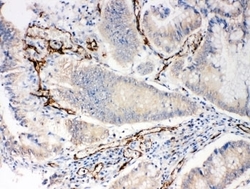

Supportive validation

- Submitted by

- NSJ Bioreagents (provider)

- Main image

- Experimental details

- IHC-P: CD31 antibody testing of human intestinal cancer tissue